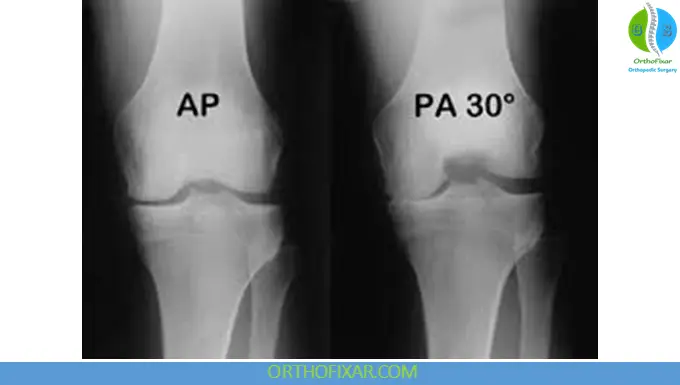

- Standing PA view (30° flexion)

Weight-bearing views are particularly important in assessing joint space narrowing and alignment.

Weight-bearing AP radiographs in 30° flexion are recommended for suspected degenerative disease. Stress AP views may demonstrate medial or lateral gapping consistent with ligamentous instability.

Fixed Flexion Posteroanterior View

Obtained at 10°–30° of knee flexion, this view is the most sensitive projection for detecting early joint space narrowing in osteoarthritis.